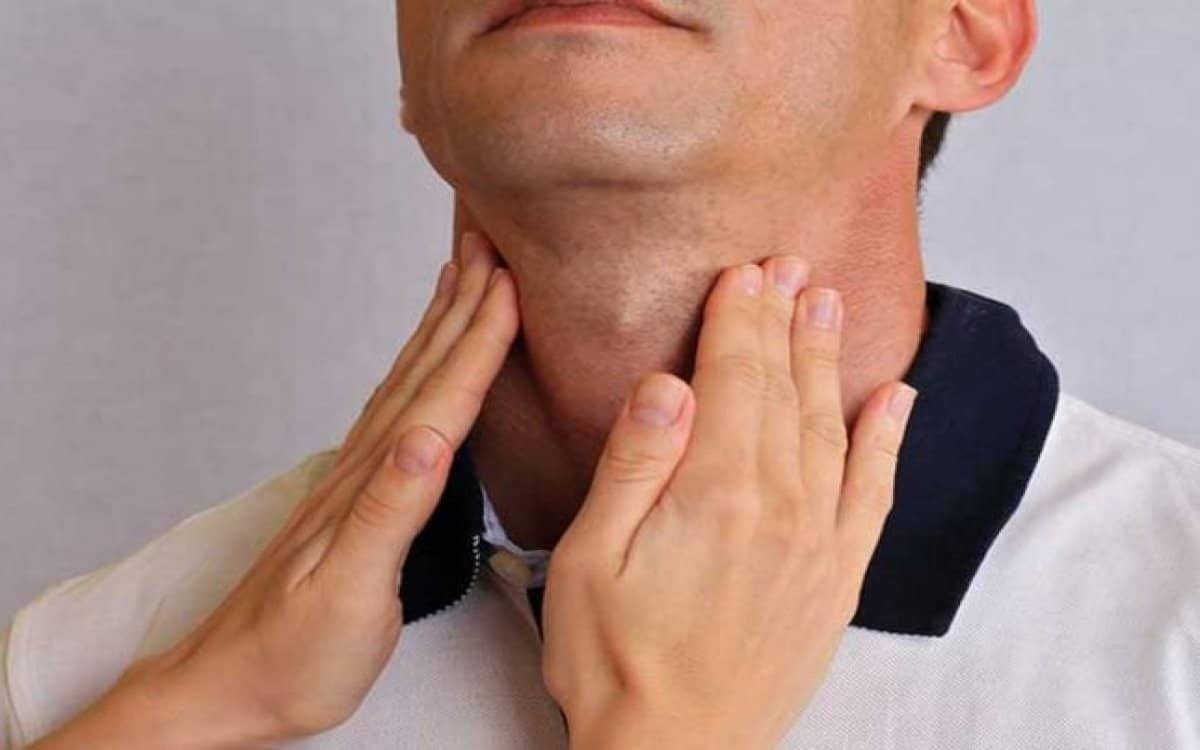

- وقد يكون السبب الإصابة بمشكلات معينة في الغدة الدرقية.